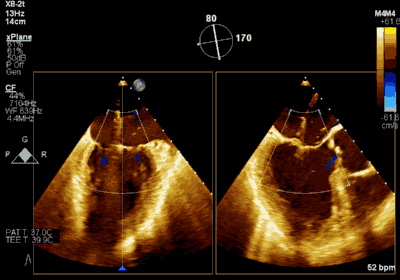

患者为73岁老年男性,既往合并冠心病、持续性心房颤动、肾功能不全病史,此次主诉“反复胸闷气促3月余”入院。诊断:心脏瓣膜病 二尖瓣脱垂伴重度关闭不全 心功能Ⅲ级(NYHA分级)。术前经胸超声心动图示:左房扩大,二尖瓣前后叶冗长、P2脱垂合并重度反流(Type II类 DMR/MR4+)。心脏测值:LA 54 x 58mm,LVD 60mm,EF% 60%,PASP 36mmHg。经食管超声心动图示:二尖瓣环左右径38mm,反流束缩流颈宽度为8.5mm,EROA 0.72cm2(PISA),舒张期二尖瓣口平均跨瓣压差2mmHg。

▲ 术前超声检查显示重度二尖瓣反流

▲ 术后超声检查显示轻度二尖瓣反流